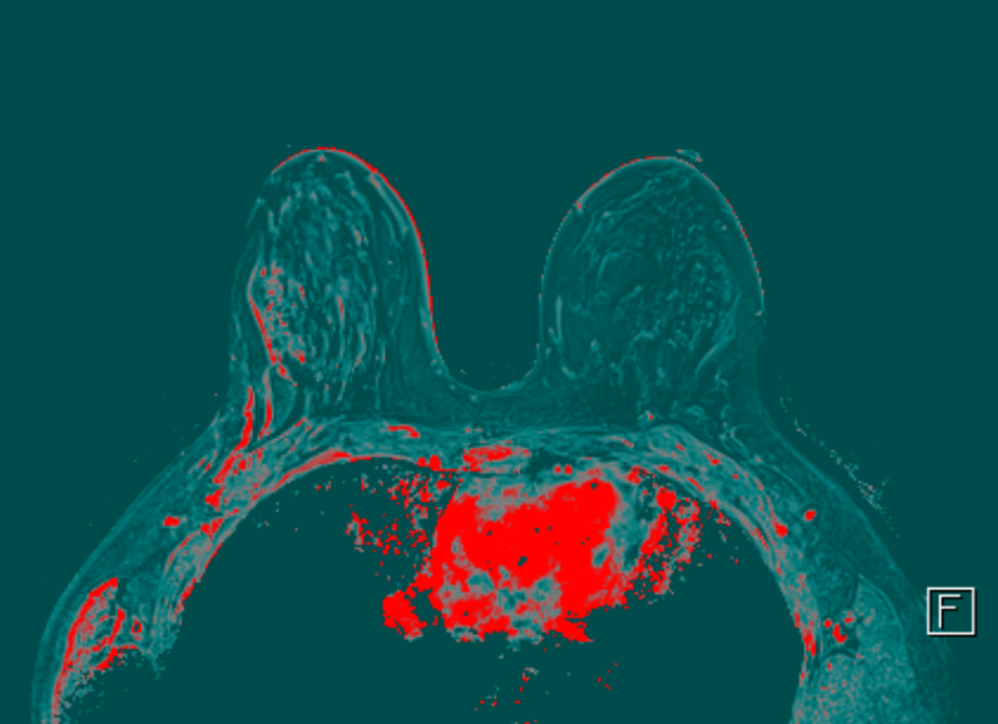

Հաջորդիվ իրականացվել է ռենտգեն մամոգրաֆիա և կրծքագեղձի ՄՌՏ հետազոտություն:

Հետազոտությունների արդյունքում՝ բուժառույի մոտ ախտորոշվել է աջ կրծքագեղձի տարածուն DCIS (կրծքագեղձի ծորանային կարցինոմա in situ)